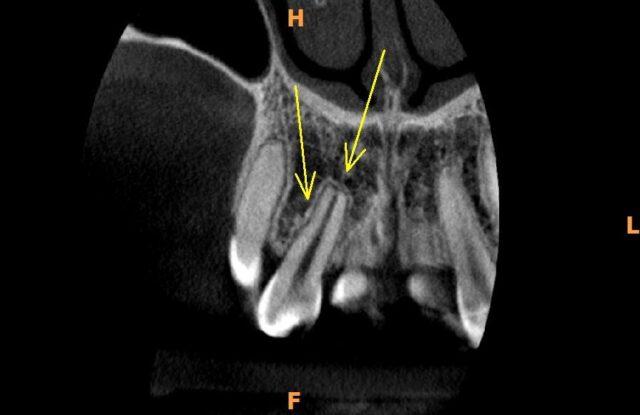

A reabsorção externa refere-se à perda progressiva do tecido duro (dentina e cemento) devido à ação de células chamadas odontoclastos, que começam a agir de fora para dentro do dente. Esse processo pode ser assintomático no início, mas se não for detectado e tratado a tempo, pode levar à perda do dente.

- Cistos e Tumores: Certos cistos ou tumores bucais podem provocar a reabsorção nos dentes adjacentes à sua localização.